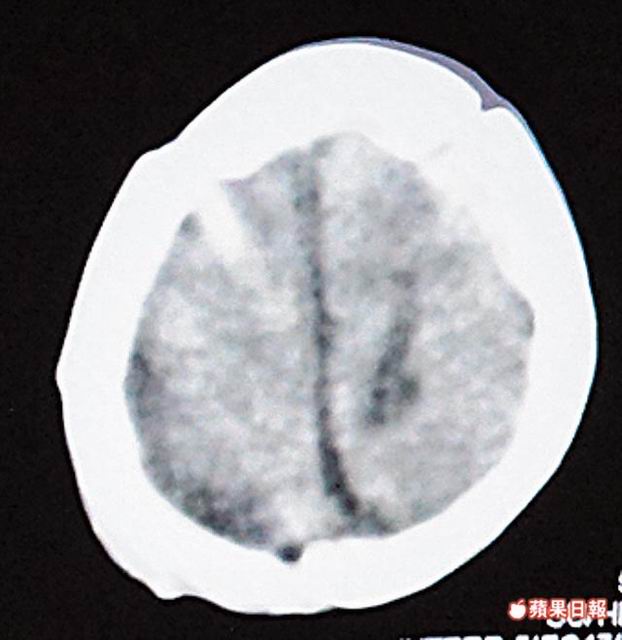

南投竹山秀傳醫院以電腦斷層掃描儀為母猴檢查。圖2為檢查影像。特生中心提供

獸醫尋求人類醫學協助,上月七日將母猴送到秀傳做斷層掃描,再由陳建民診斷。陳說,母猴腦部有零星出血點,建議不需開刀,讓出血點慢慢吸收即可。